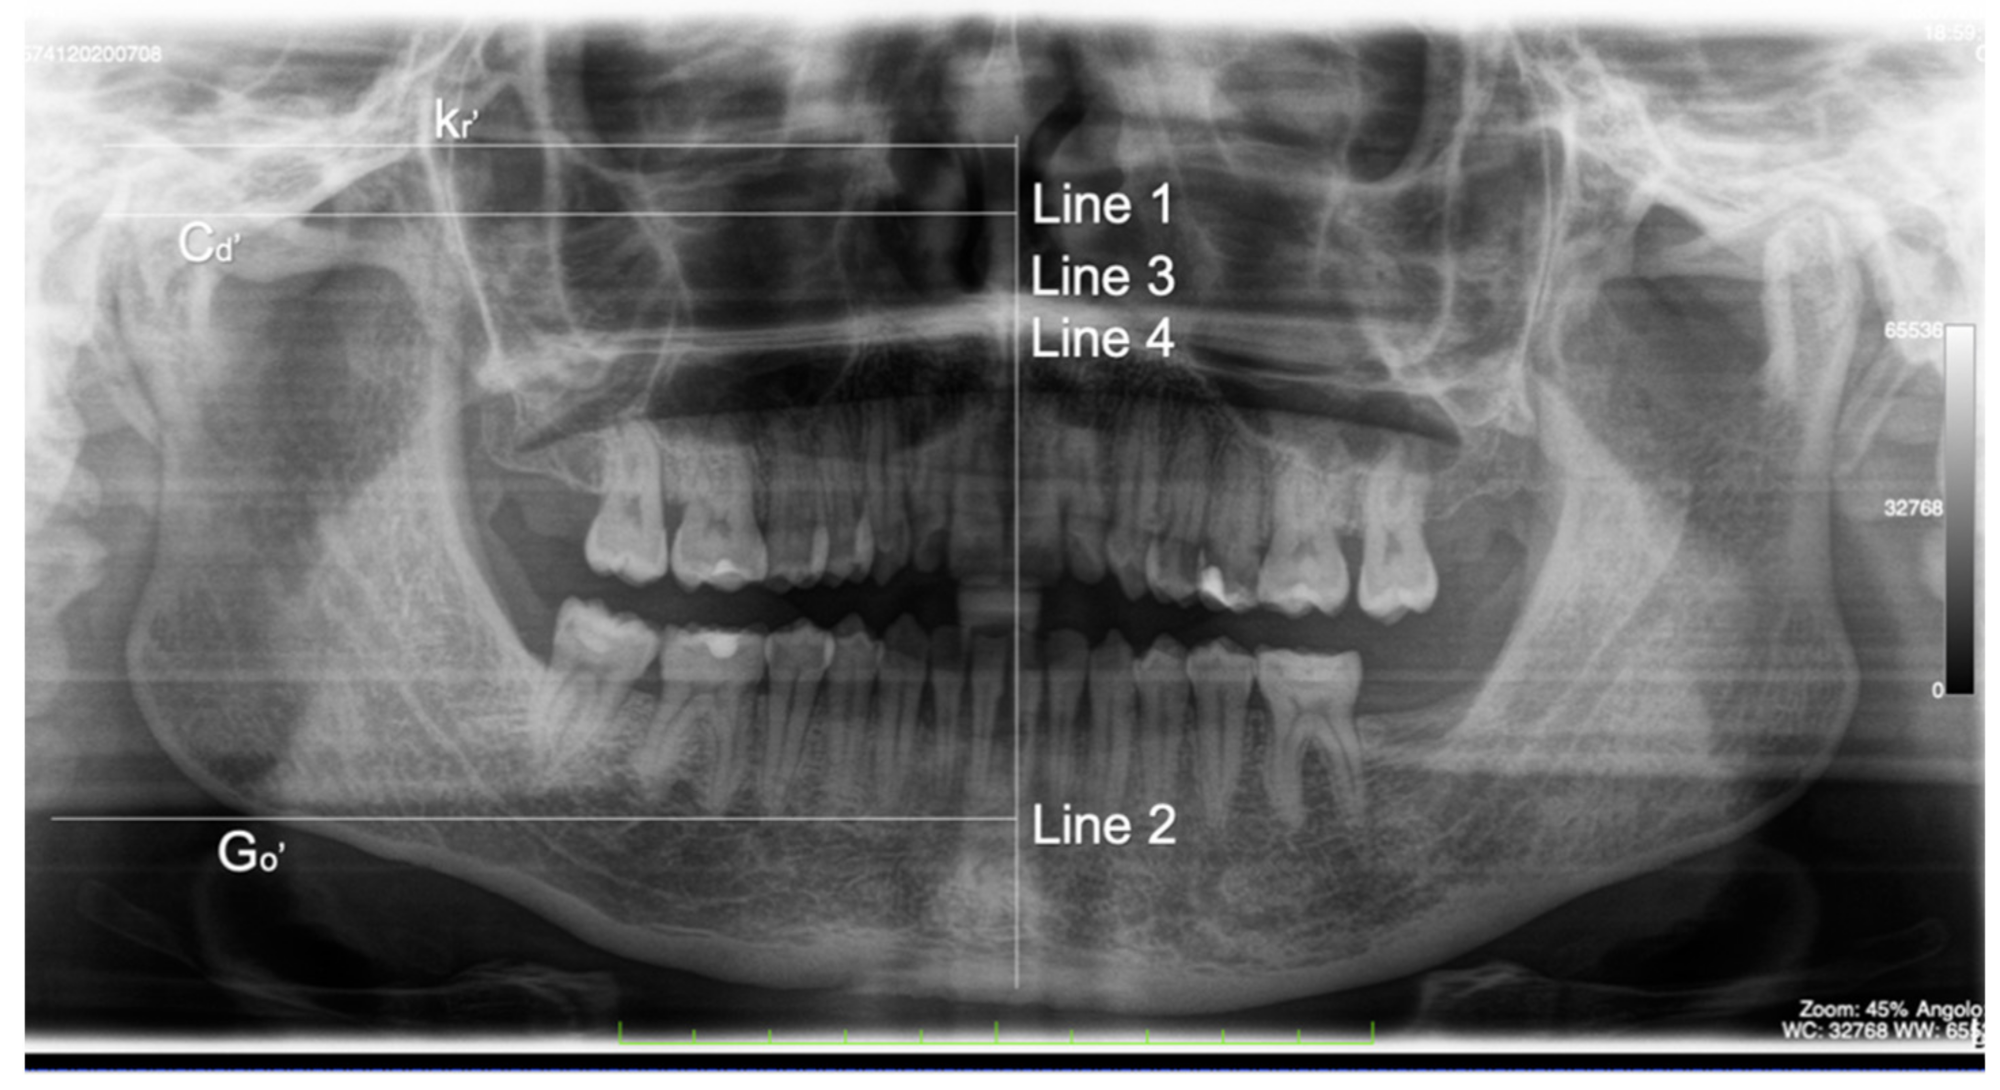

- Kubota, Y.; Takenoshita, Y.; Takamori, K.; Kanamoto, M.; Shirasuna, K. Levandoski panographic analysis in the diagnosis of hyperplasia of the coronoid process. Br. J. Oral Maxillofac. Surg. 1999, 37, 409–411. [Google Scholar] [CrossRef]